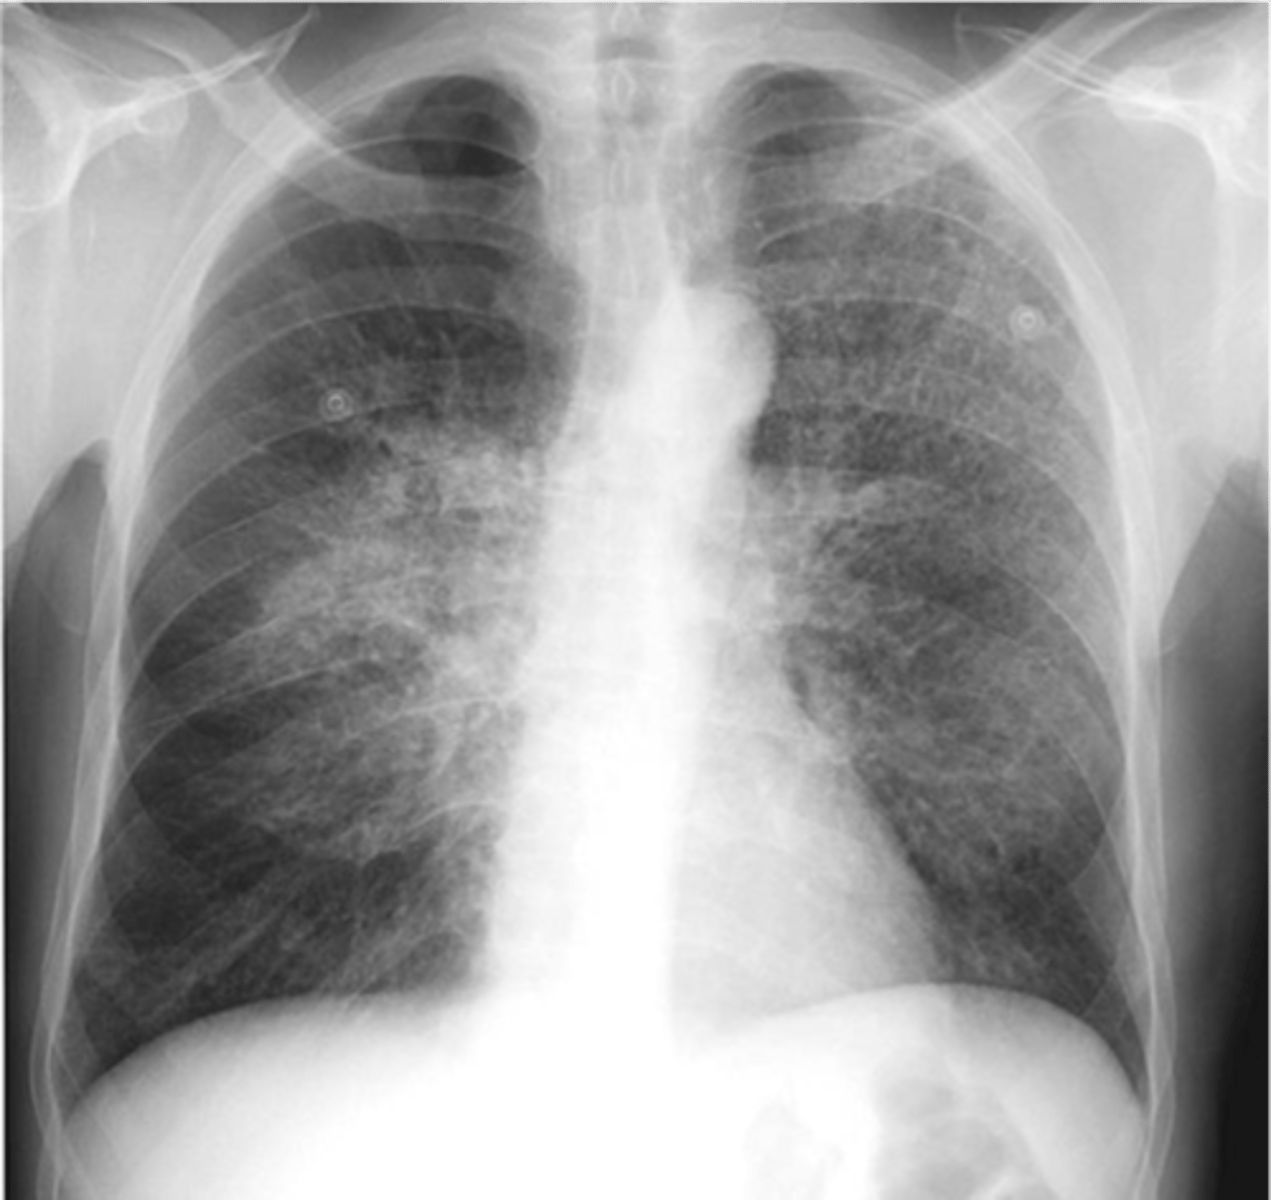

-b/l perihilar airspace disease with diffuse interstitial markings

-kerley B lines

(PICTURE ON LEFT)

Pulmonary edema appearance